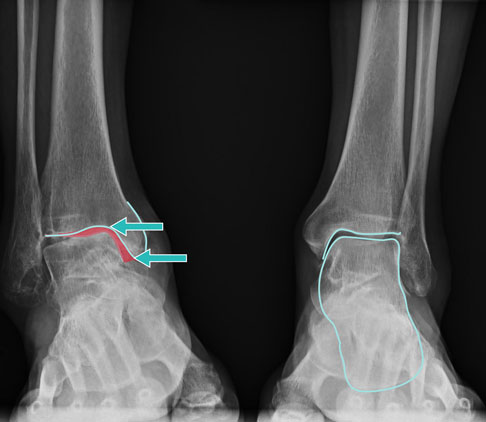

Bei dieser Varusarthrose ist es zu einem Defekt am Innenknöchel gekommen. Hier muss eine individuelle Behandlungsstrategie erstellt werden, z. B. mit Implantation einer Sprunggelenksprothese. © Gelenk-Klinik

Die Valgusstellung des Fersenbeins (X-Stellung bzw. nach innen geknicktes Gelenk, rot) ist eine Fehlstellung des Sprunggelenks. Die Folge kann eine Sprunggelenksarthrose sein. Auch für die Haltbarkeit einer Sprunggelenksprothese ist eine Fehlstellung ungünstig. © Gelenk-Klinik

Röntgenbild vor der Operation (links): Durch Arthrose hat sich das Sprungbein verformt (türkis markiert). Röntgenbild nach der Operation mit Sprunggelenksprothese (Mitte). Die Prothese stellt die normale Form des Sprungbeins (Talus) wieder her und gewährleistet eine gleichmäßige Kraftverteilung ohne Kanten und Ecken (rote Pfeile). © Gelenk-Klinik